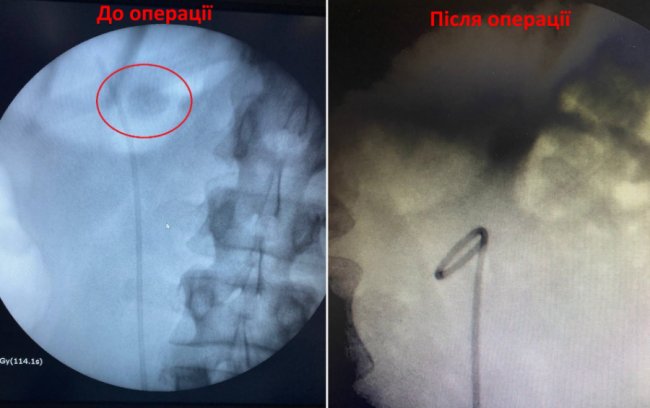

Немісцевий молодий чоловік, який довго хворів сечокам’яною хворою, вперше звернувся у Центр ендоурології та літотрипсії Ковельського МТМО зі скаргами на болі в попереку, які турбували його досить тривалий час. Як наслідок - камінь у лівій нирці досяг загрозливих розмірів - 23 міліметри, що спричинило анатомічну зміну будови нирки.

Лікарі кажуть, що втрачений час міг коштувати 33-річному пацієнту втрати життєво важливого органу. Тож ковельські медики у найкоротші терміни провели усі необхідні обстеження. Урологи Зубок М.О. та Гаврилюк М.І., зробили малоінвазивну операцію PCNL (черезшкірну нефролітотрипсію), подробивши та забравши камінь через невеликий розріз.

Операція пройшла успішно та безболісно для хворого. Нирку врятували Пацієнт почувається добре та уже виписаний з лікарні.